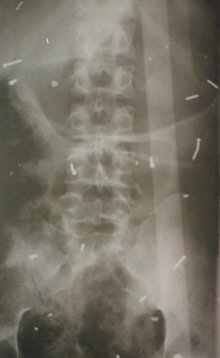

An abdominal radiograph of Nema, the mother, might well have been this. Image 4